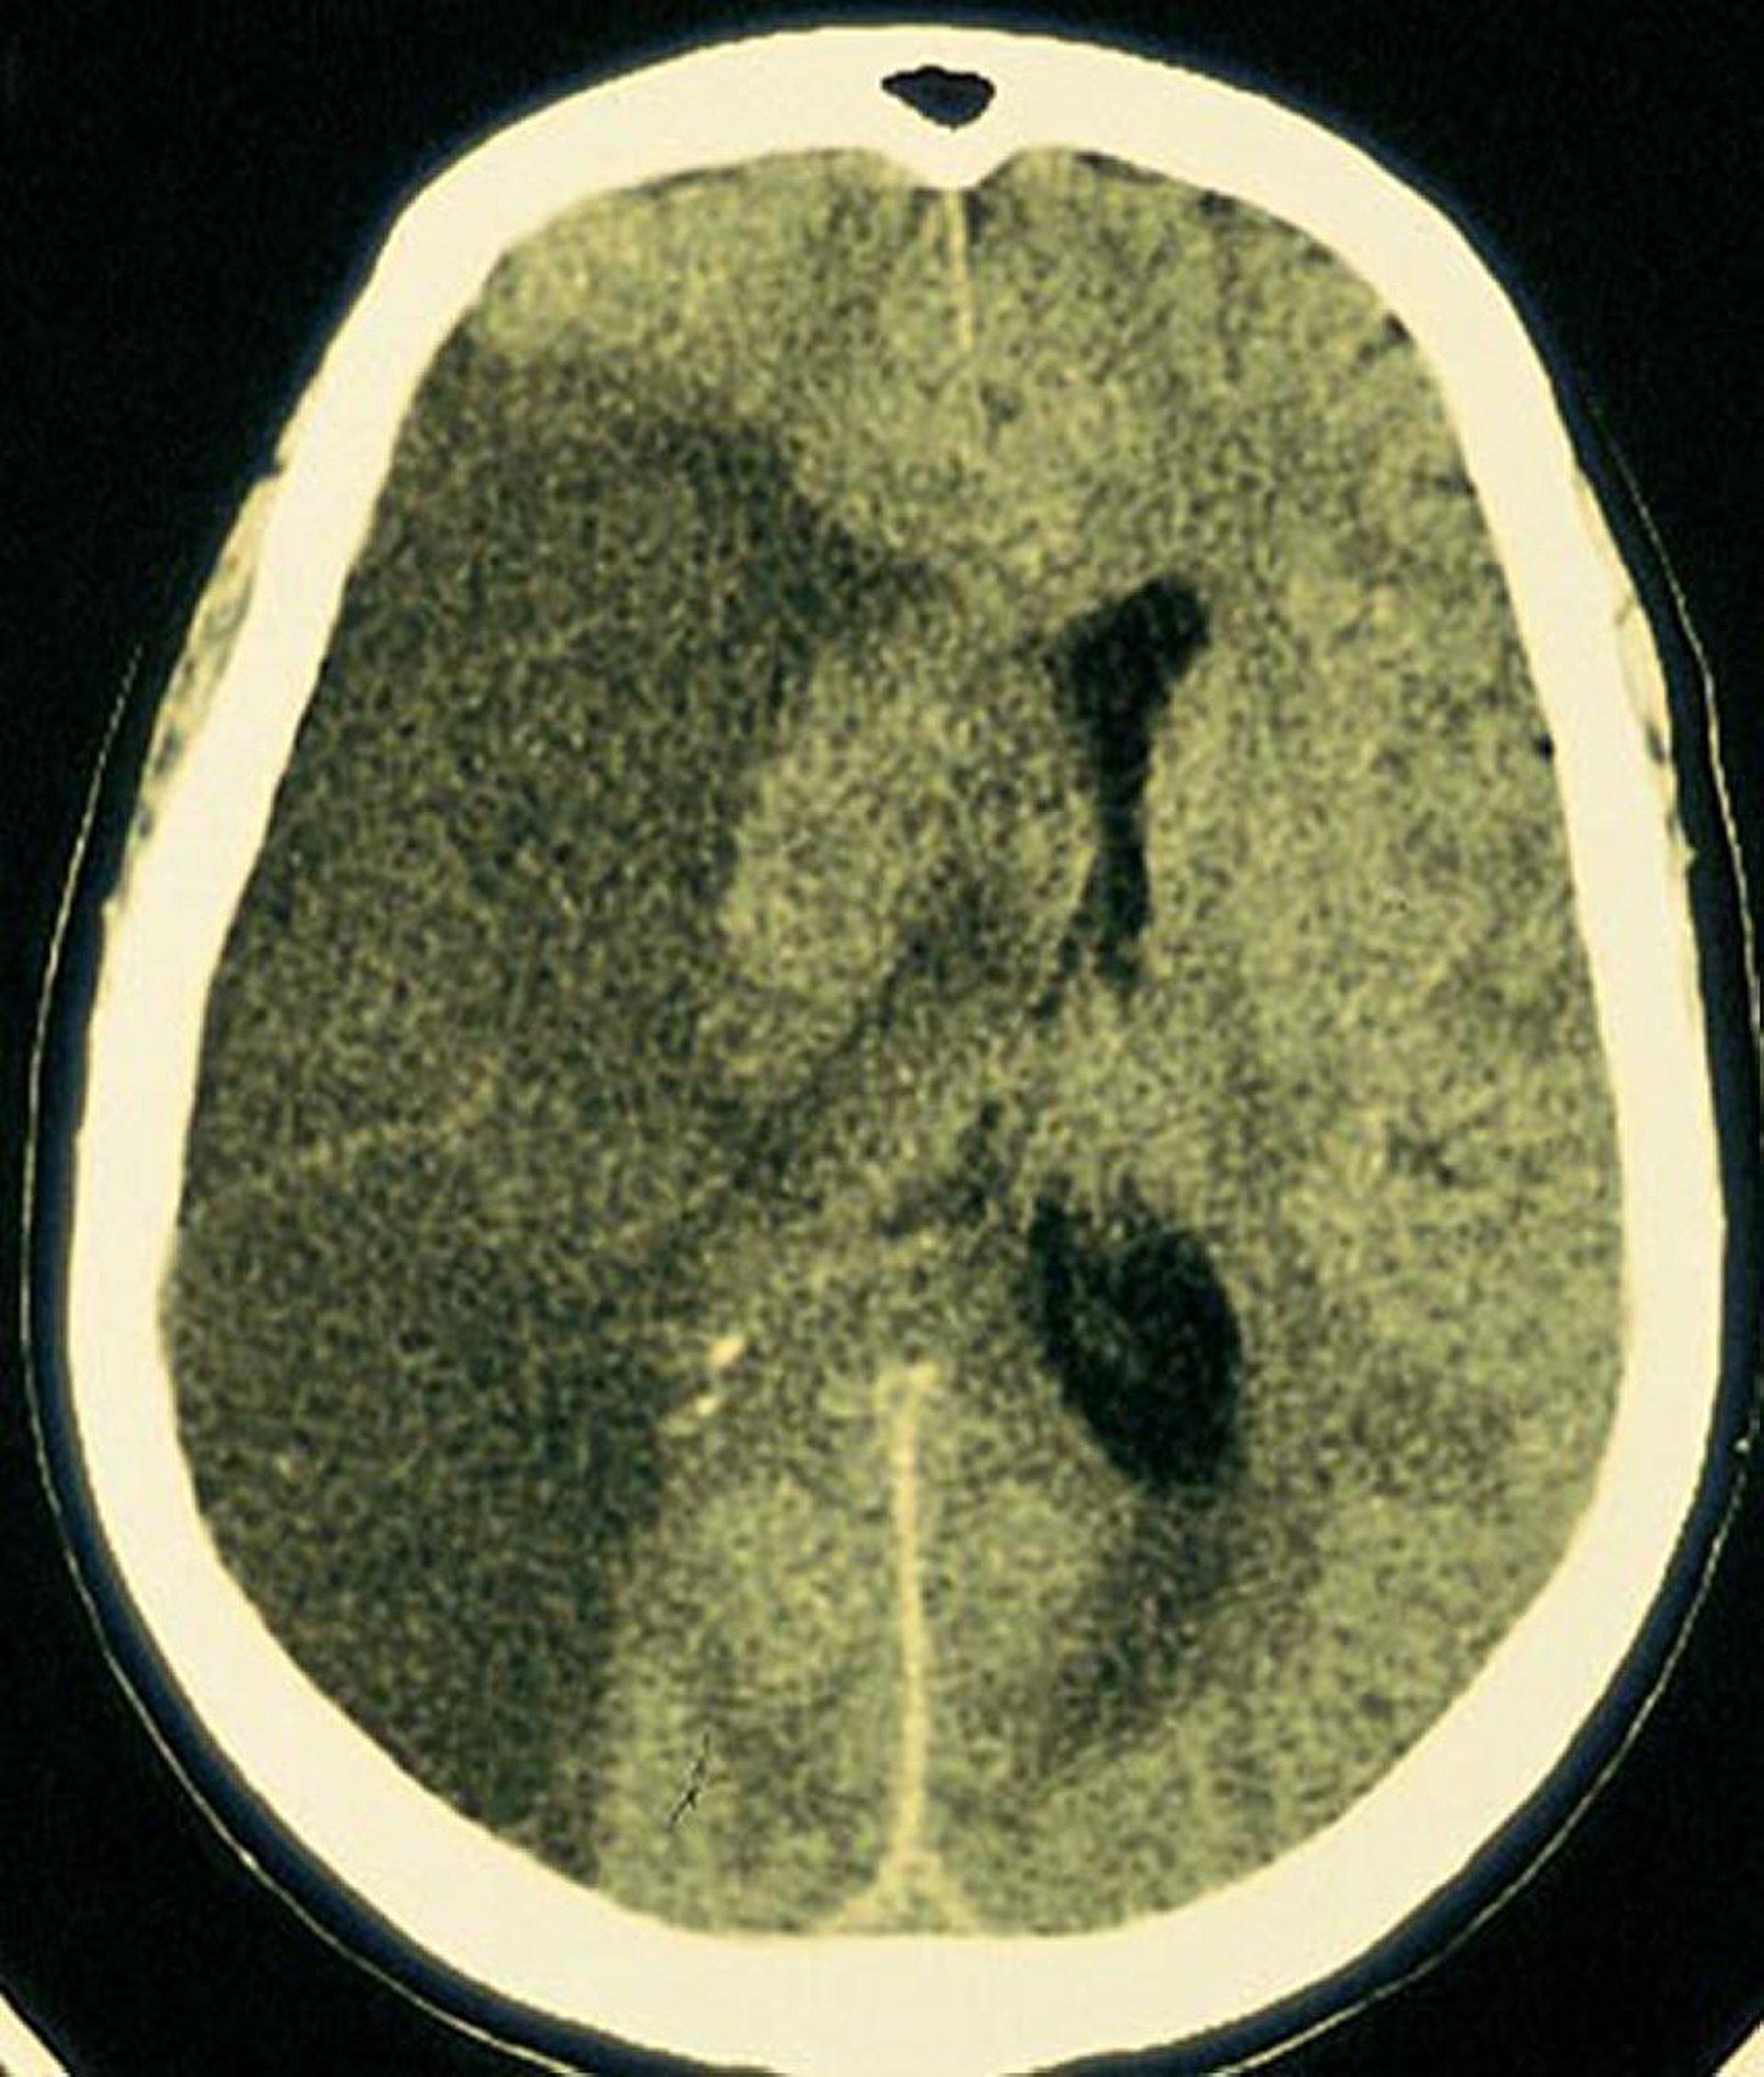

Infarctus de l'artère cérébrale moyenne (fréquent)

Un grand infarctus est visible dans la région du cerveau alimentée par l'artère cérébrale moyenne droite.

By permission of the publisher. From Furie K, et al: Cerebrovascular disease. In Atlas of Clinical Neurology. Edited by RN Rosenberg. Philadelphia, Current Medicine, 2002.